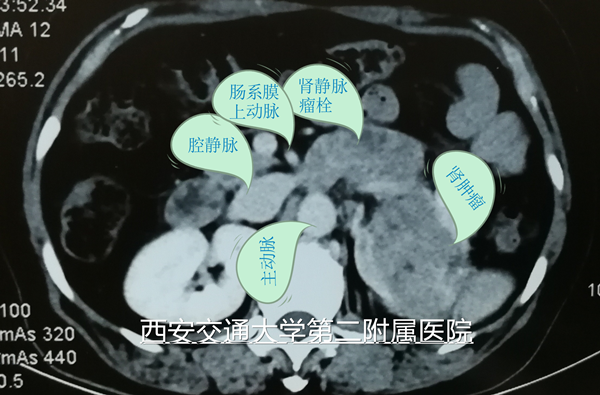

2018年5月18日,西安交通大学第二附属医院泌尿外科成功完成一例经腹膜后腔镜左肾并肾静脉瘤栓根治性切除术。该病例患者为中年女性,以血尿20余天主诉入院,入院检查发现左肾有直径约10cm肿瘤,同时左肾静脉有瘤栓形成,瘤栓近端超越肠系膜上动脉水平,接近下腔静脉。入院检查未发现远处转移征象。根据循证医学证据,如能够成功进行左肾根治并瘤栓切除 ,将显著延长患者生存期、甚至达到治愈水平。

按照以往经验,该手术需要开腹,切口长约30cm,同时由于肾静脉瘤栓阻塞,侧支血管常处于充血怒张状态,术中极易损伤血管甚至导致大出血。近年随着腹腔镜手术开展,合并瘤栓的肾切除也逐步开展,目前这也是国内一流泌尿外科的标志性手术,泌尿外科也进行了多例瘤栓取出手术。但对于超越肠系膜上动脉水平的左肾静脉瘤栓,国内外腔镜手术的主流做法是术前进行左肾动脉栓塞,术中先右侧入路紧贴腔静脉结扎肾静脉,再变换体位左侧入路行左肾切除。这样虽然可以通过腔镜技术完成手术,但手术费用、手术时间及术中出血的机率都明显增加。

5月18日手术当天,麻醉科吕建瑞主任、李卫松医生,手术室吴莉娜、孙楠与主管医生李洪亮再次沟通,明确手术难点、风险、注意事项以及术中可能用到的各项特殊用品。手术由李洪亮副主任医生主刀、李刚主治医生一助、住陪医生尉博、赵阿孟辅助,种铁主任对该手术非常重视,全程台下进行指导,及时指出术中的注意事项。术中通过合理设计、精细解剖、充分显露左肾静脉与主动脉、肠系膜上动脉,最终顺利按计划通过左侧腹膜后入路腔镜下完成手术。术中无明显出血,麻醉复苏顺利,手术当晚查房患者精神状态非常好,术后第一天患者已经下地活动,肠功能恢复,并开始正常饮食。目前患者恢复顺利,患者及家属对我院的医疗技术水平表示非常满意。